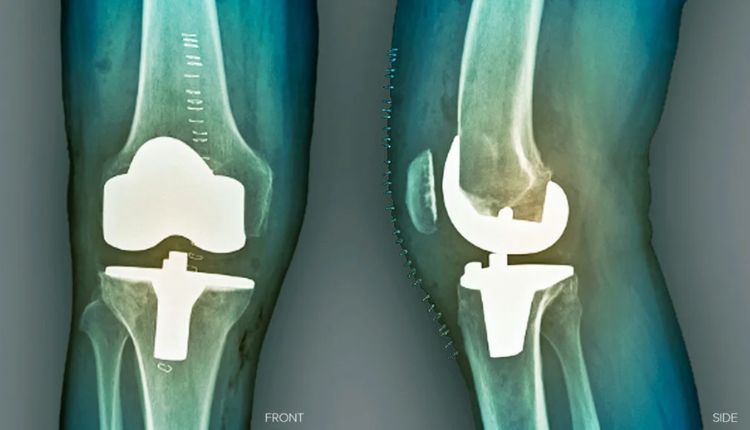

Major bone or joint surgery can feel like a long road, both physically and emotionally. Whether it is a knee replacement, hip surgery, or a complex fracture repair, the days and weeks after the procedure are just as important as the surgery itself. Recovery is not only about healing the body but also about learning how to move, rest, and care for yourself again.